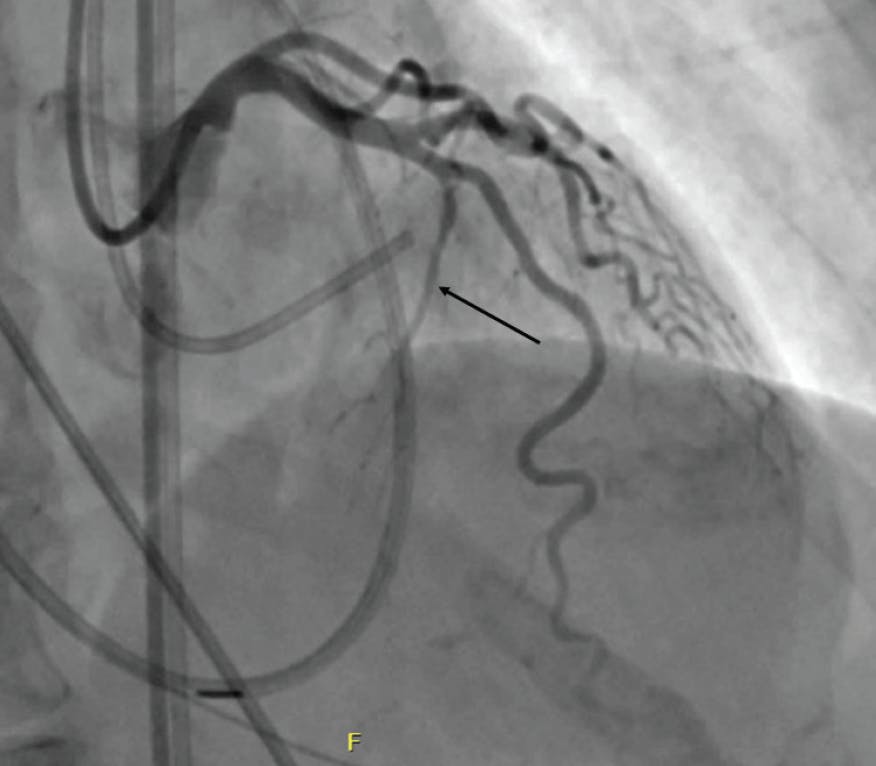

A careful review of the echocardiogram should confirm significant obstruction (> 50 mm Hg at rest or with provocation), systolic anterior motion (SAM) of the mitral valve, and “adequate” septal thickening (usually ≥ 1.5 mm). Most importantly, the septal anatomy requires careful review. The ideal anatomy is a proximal first septal perforator from the left anterior descending artery (LAD) that is about 1.5 mm in diameter and reaches not much farther than the midseptum (Figure 1). However, septal anatomy varies greatly, and some varieties are not suitable for ASA. For example, there may be an array of very small septals, or the proximal septals may be too small to instrument or unlikely to supply the correct place in the septum to eliminate obstruction (Figure 2). Alternatively, there may be a single, very large septal perforator that supplies a large amount of nontargeted myocardium (Figure 3). Note that septal perforators may arise from vessels other than the LAD, including the proximal diagonal, ramus, left main, and even right coronary arteries. The operator should review the baseline electrocardiogram. Because a right bundle branch block occurs in 40% of patients undergoing ASA, a pre-existing left bundle branch block is associated with a very high risk for permanent pacemaker.

Figure 1. Example of a suitable first septal perforator for performance of ASA (arrow).